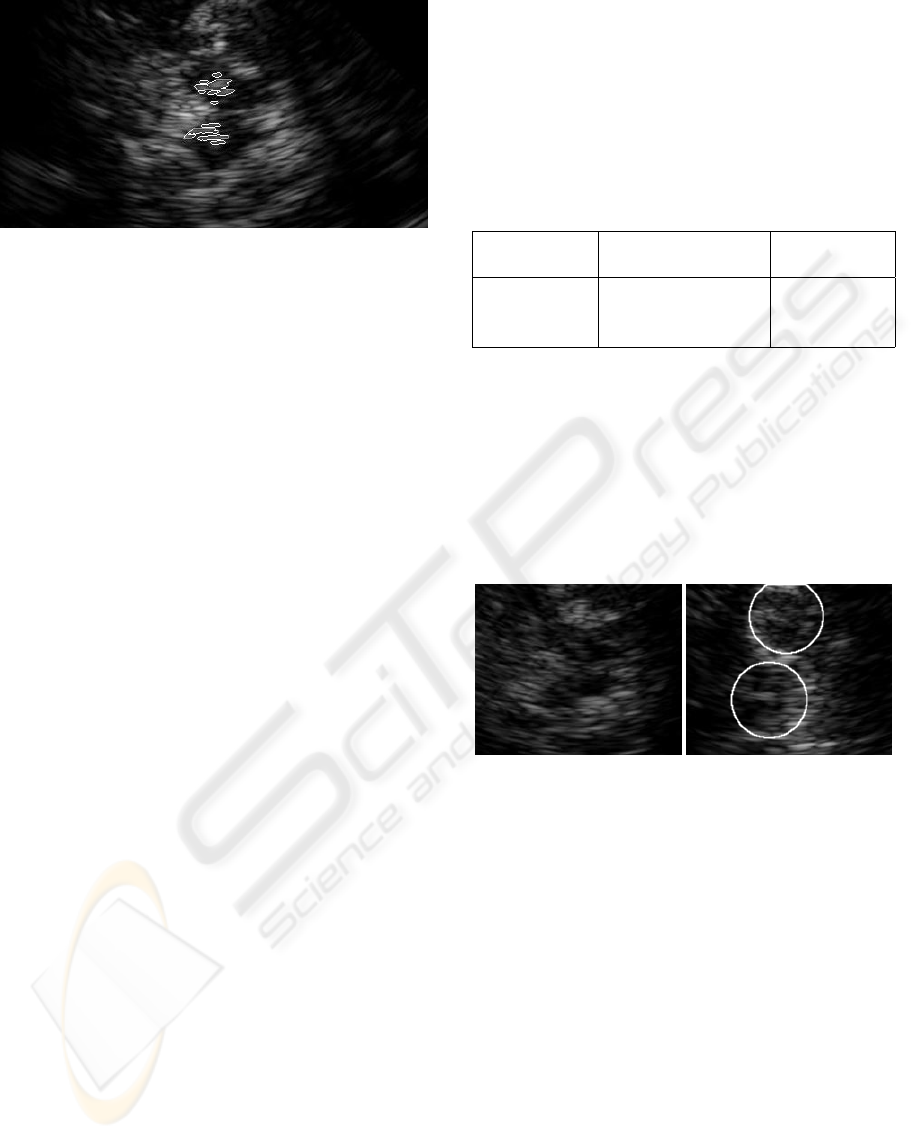

Our method may be divided into two phases. At

first, it attempts to correctly identify the position of

brain stem in processed image. This phase is crucial

in overall diagnostics and this paper focuses mostly

on this part. In the second phase, we detect the ob-

jects of interest in the brain stem. The detection of

existence, shape, size, and echogenicity of these ob-

jects is a valuable contribution to the diagnostics of

Parkinson’s disease.

Achieved results obtained during testing make us

believe that the method we have developed for the de-

tection and analysis of the brain stem in transcranial

ultrasound images is successful. From the tested im-

ages, we obtained good results. In 76% of cases, the

position of the brain stem was correctly determined.